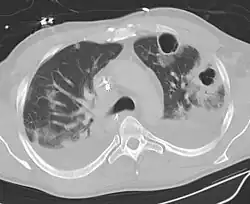

| Computed tomography (CT) scan of chest showing bilateral pneumonia with abscesses, effusions, and caverns. 37-year-old male. | |

Pulmonary abscess on CT scan -